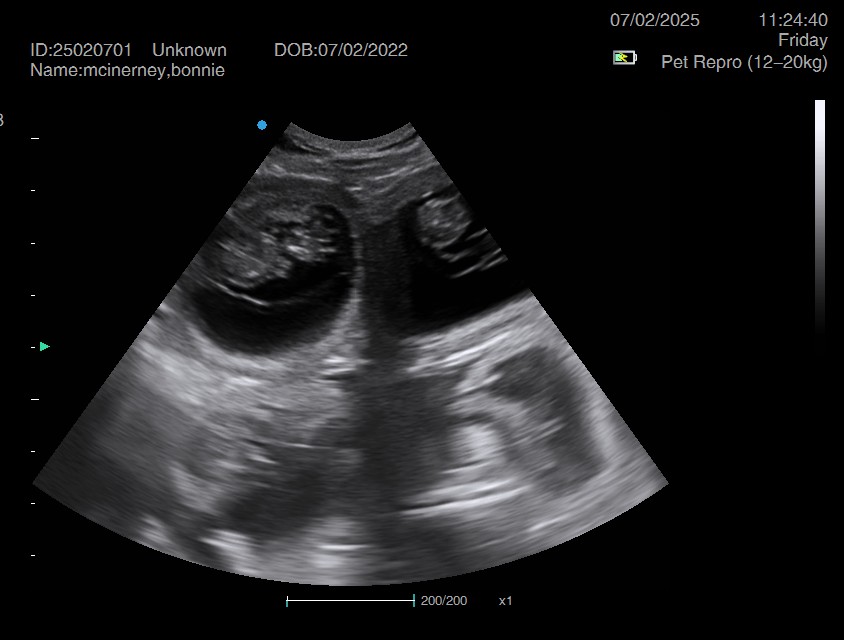

Ultrasound pregnancy scanning is a safe, non-invasive way to confirm pregnancy in dogs and cats, offering breeders and pet owners peace of mind and vital information to support responsible care. It allows us to detect gestational sacs, assess foetal development, and estimate litter size—all while ensuring the wellbeing of the animal.

Pregnancy can sometimes be detected as early as Day 18 post-mating, but scanning at this stage is not routinely recommended. Embryos are still developing and may not be clearly visible, and there is a natural risk of embryo resorption, which can lead to misleading or inconclusive results.

For the most accurate and reliable scan, we advise booking between Day 25 and Day 32, when pregnancy is more easily confirmed and foetal structures are clearer. If an early scan is performed and no pregnancy is detected, we offer a FREE complimentary re-scan after 7 days at the clinic to ensure clarity and support informed decision-making.

Our approach balances early insight with ethical care—always prioritizing the comfort of the animal and the accuracy of the results.